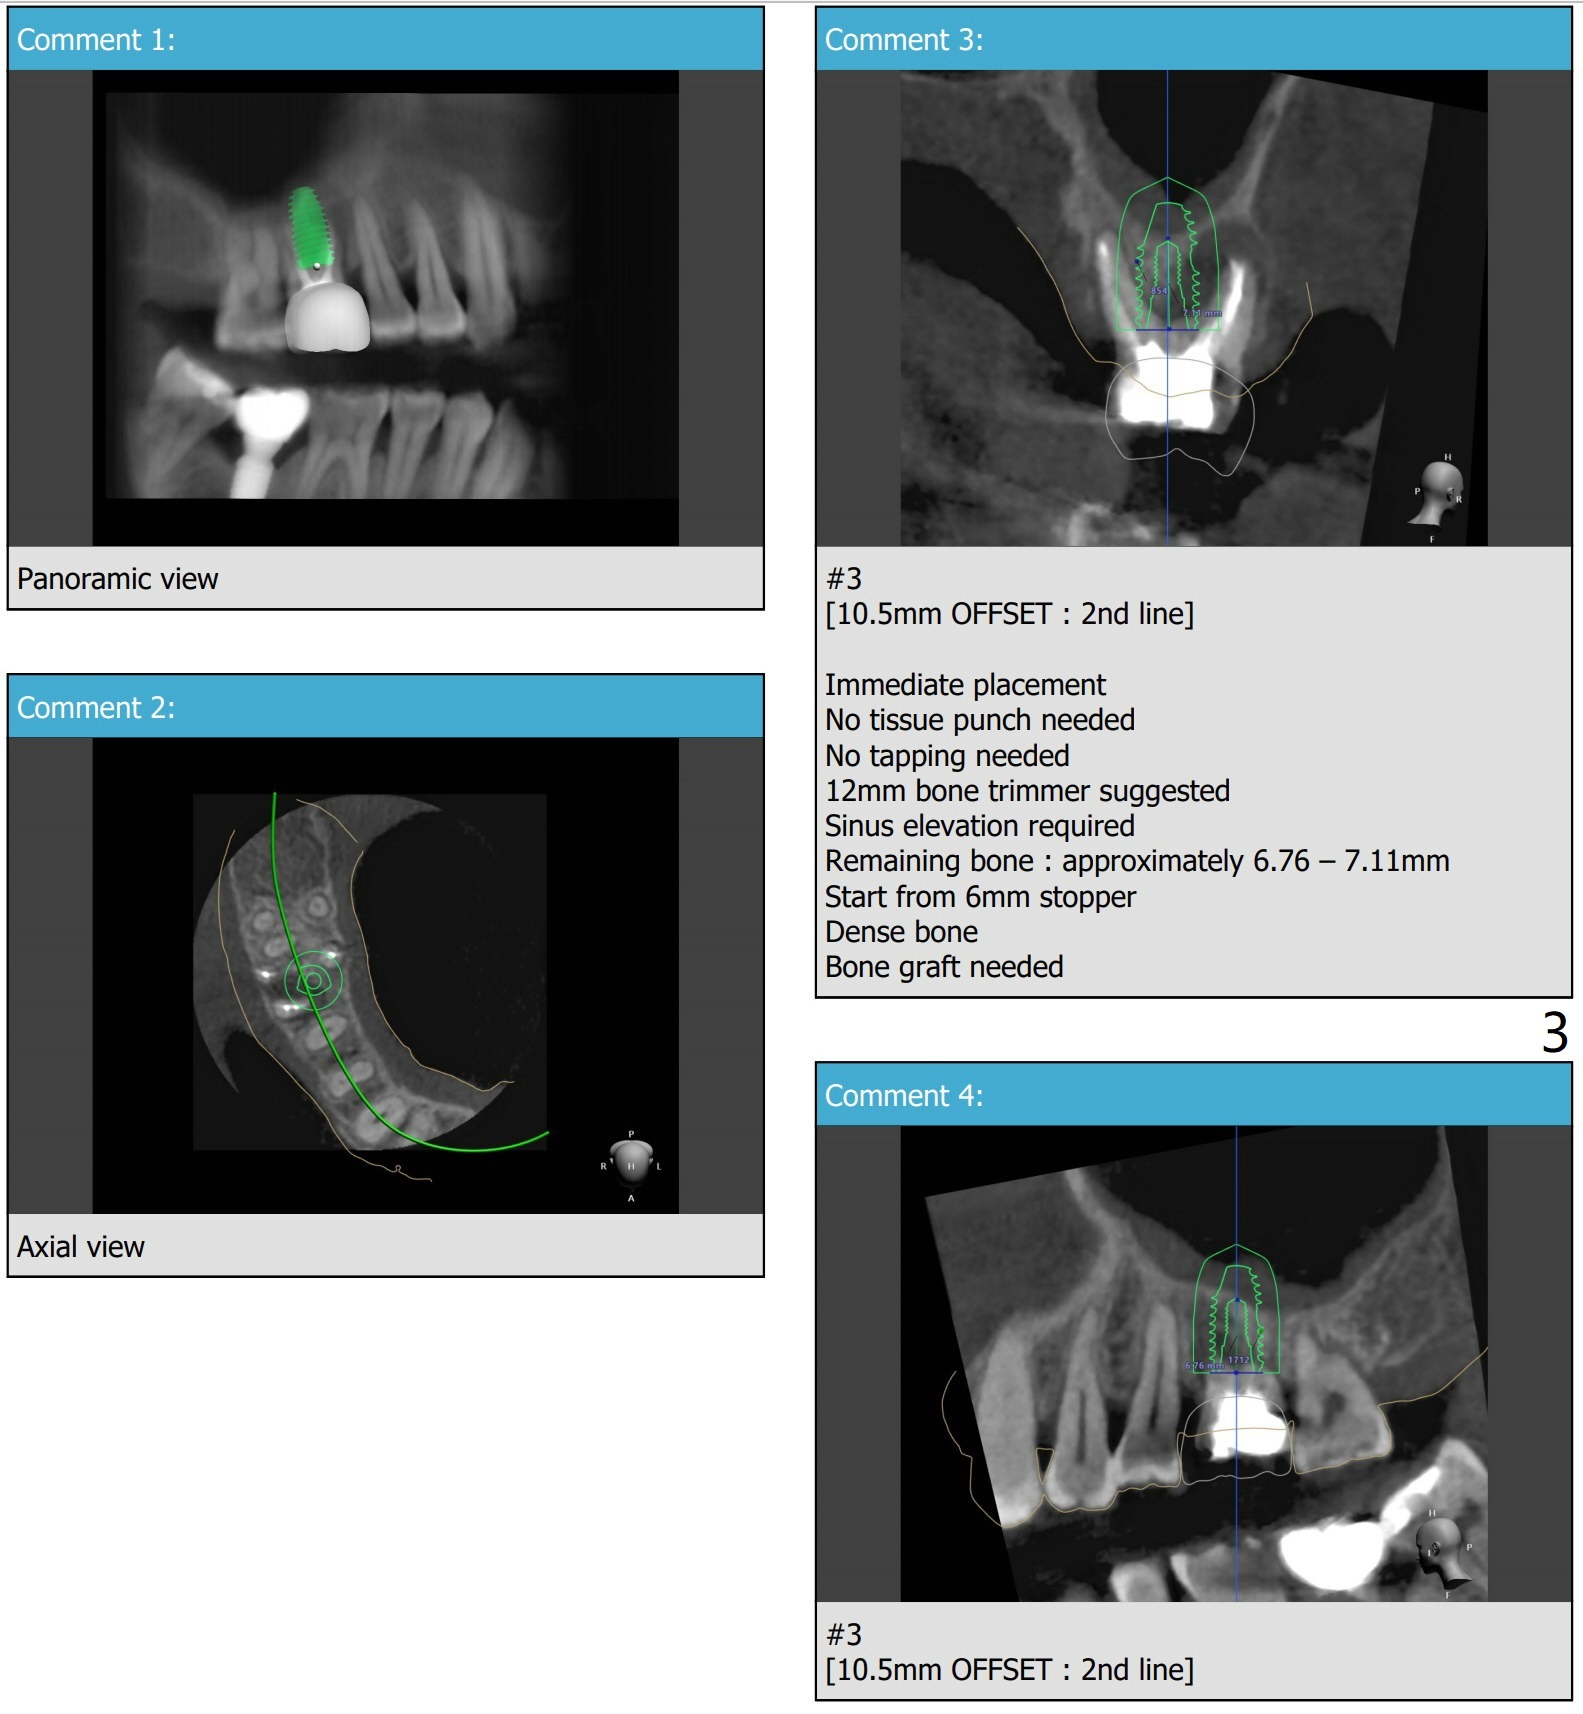

Return to No Caries  手术

Xin Wei, DDS, PhD, MS 1st edition 12/04/2020, last revision 12/17/2020